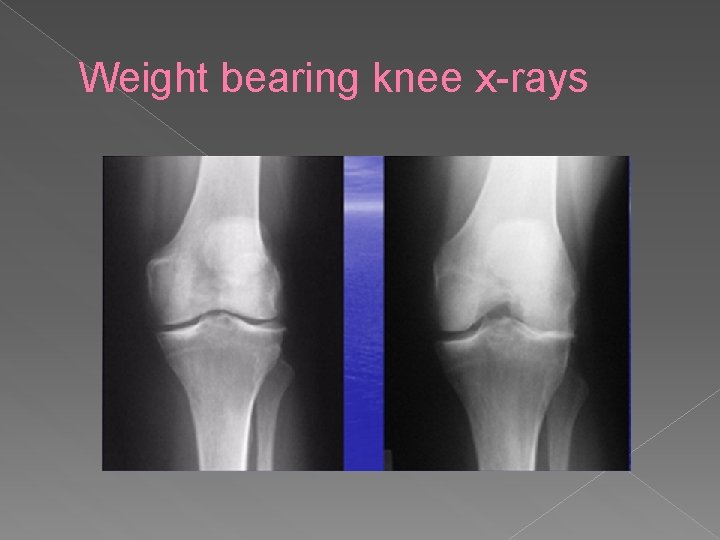

Weight bearing knee x-rays